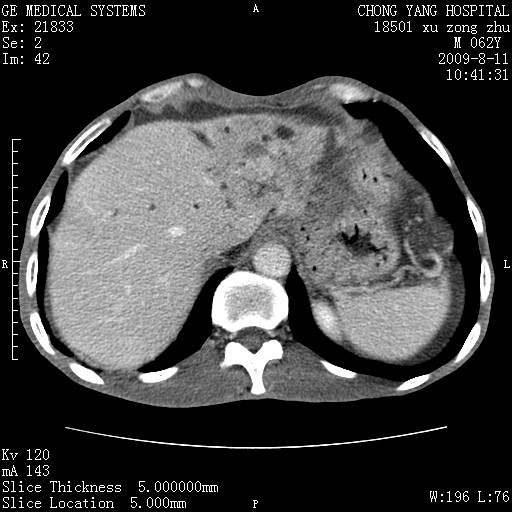

以下是引用杀毒软件在2009-8-11 16:35:00的发言:[br]肝内胆管扩张局限于左叶,胆管内有结石伴肝外胆管结石,胆管壁增厚呈弥漫性并发腹腔积液,胰腺边界模糊。[br][br]考虑---胆总管及肝内胆管结石继发胆管炎及胰腺炎,左肾下极囊肿,腹水。

以下是引用zjzjr在2009-8-11 17:35:00的发言:[br]肝内胆管扩张局限于左叶,胆管内有结石伴肝外胆管结石,胆管壁增厚呈弥漫性并发腹腔积液。[br][br]考虑---胆总管及肝内胆管结石继发胆管炎,左肾下极囊肿,腹水。